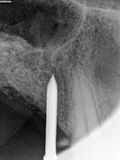

fredlibc | all galleries >> Galleries >> JGolo - urq implants > R8.jpg

R8.jpg